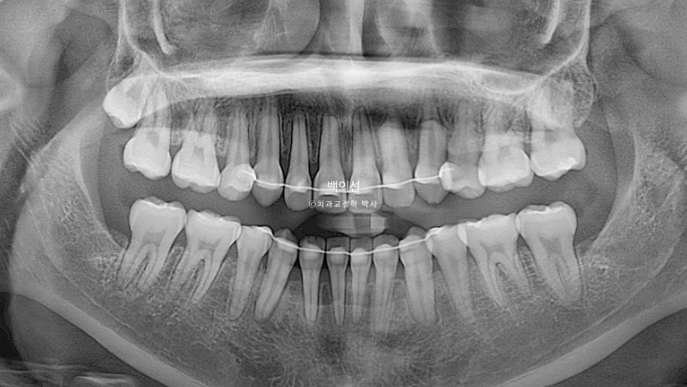

앞니 한두개에 경미한 치근흡수가 보입니다.

치근 평행도는 양호합니다.

치아끼리 심하게 겹쳐져 있던 부위에 블랙트라이앵글은 아쉽지만 잇몸이 내려가 있었던 다수의 치아들에서 잇몸이 다시 차오른 것을 볼 수 있습니다.

통상 한 번 내려간 잇몸은 다시 차오르지 않는다고 알려져 있지만

잇몸이 내려간 원인이 만약 치아가 자리가 없어 밀려나 있었기 때문이라면, 발치교정을 통해 밀려난 위치에서 안정적인 위치로 움직이는 과정에서 잇몸이 다시 차오를 수 있습니다.